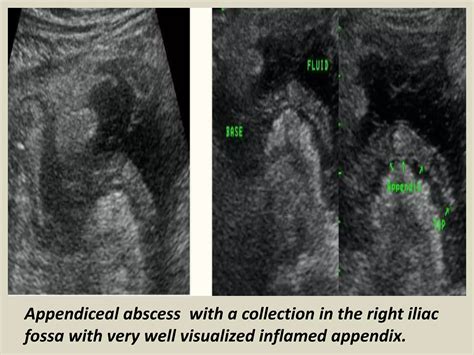

• Periappendiceal Fluid: The presence of fluid around the appendix can indicate inflammation or infection.